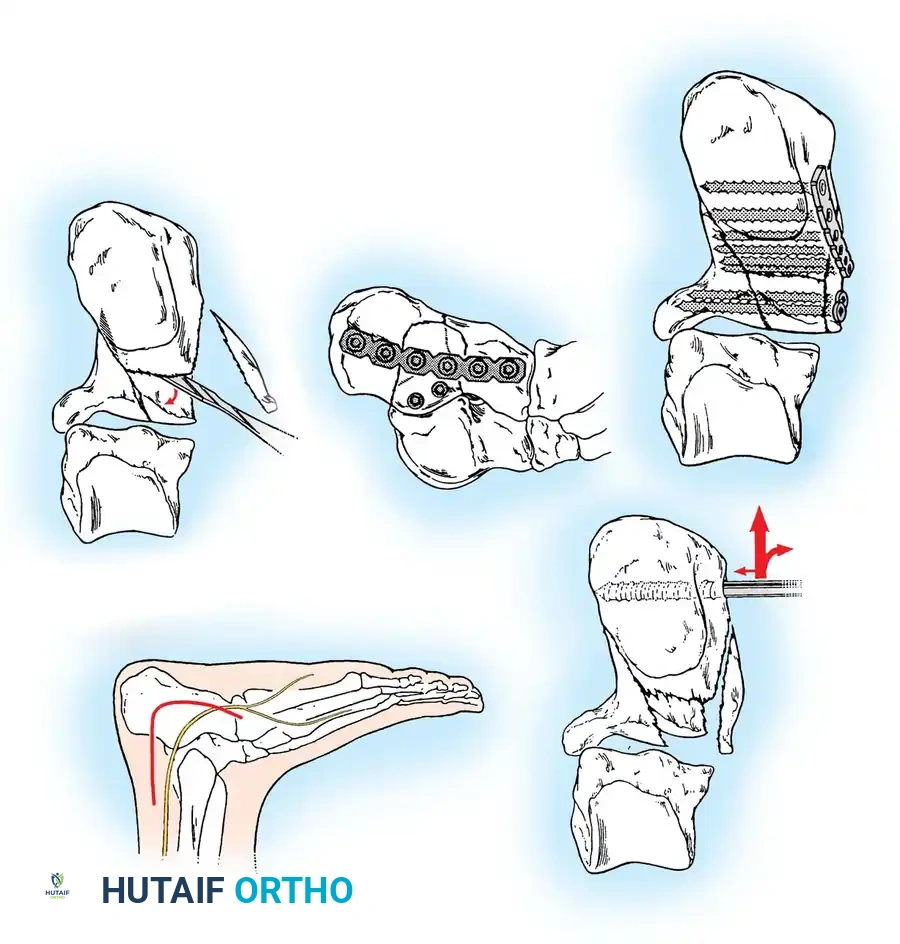

The Extensile Lateral Approach

The workhorse for calcaneal ORIF is the extensile lateral approach.

- Positioning: The patient is placed in the lateral decubitus position. A thigh tourniquet is applied.

- Incision: An L-shaped incision is made. The vertical limb is placed just anterior to the Achilles tendon, and the horizontal limb is placed in line with the base of the fifth metatarsal, transitioning between the glabrous (plantar) and non-glabrous (lateral) skin.

- Flap Creation: A full-thickness subperiosteal flap is elevated. It is imperative to use a "no-touch" technique. Retraction is achieved by placing stout Kirschner wires (K-wires) into the fibula, talar neck, and cuboid, bending them to hold the flap out of the surgical field without using self-retaining retractors that crush the skin edges.

Reduction Sequence

The reduction follows a strict, logical sequence:

- Decompression: The lateral wall blowout is reflected inferiorly to expose the depressed posterior facet and the subtalar joint.

- Tuberosity to Sustentaculum: A Schanz pin is placed into the posteroinferior tuberosity. Using the pin as a joystick, the tuberosity is pulled out of varus, translated medially, and pulled plantarly to restore length, height, and alignment. It is temporarily pinned to the constant sustentacular fragment.

- Posterior Facet Reduction: The depressed articular fragments are elevated to match the intact articular surface of the talus.

- Anterior Process: If the calcaneocuboid joint is involved, it is reduced and pinned.

- Lateral Wall: The lateral wall is reduced to decompress the subfibular space, ensuring the peroneal tendons have adequate excursion.

Internal Fixation

Once anatomical reduction is confirmed via fluoroscopy (including Brodén views), definitive fixation is applied. A low-profile, anatomically contoured calcaneal locking plate is typically utilized.

Screws must be directed from lateral to medial, specifically targeting the dense bone of the sustentaculum tali to anchor the construct.

Percutaneous and Minimally Invasive Techniques

For specific fracture patterns, particularly the Essex-Lopresti Tongue-Type fractures, percutaneous reduction and screw fixation can yield excellent results with minimal soft-tissue risk.

Using the classic Essex-Lopresti maneuver, a heavy Schanz pin or Steinmann pin is introduced percutaneously into the posterior aspect of the tongue fragment. The knee is flexed to relax the Achilles tendon, and the pin is used to lever the fragment plantarly, restoring the posterior facet congruity.

Once reduced, the fragment is secured with percutaneous cannulated screws directed from the posterior tuberosity into the anterior calcaneus.